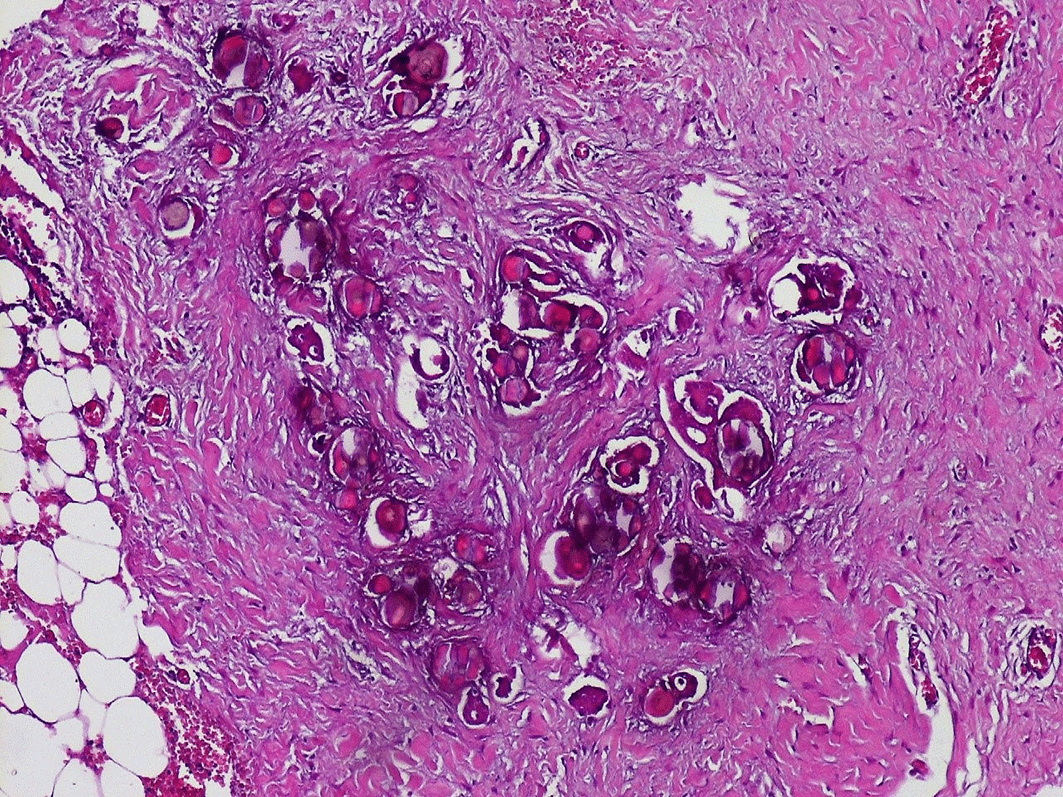

At coelioscopy, multiple nodular implants involving the omentum, the peritoneum and a magma of intestinal loops in the right iliac fossa were noted. A biopsy from nodules was performed. Gross examination showed multiple nodules of different sizes in the fat tissue. Pathologic examination showed massive psammoma bodies representing more than 75% of the tumor (see Figure 2). The epithelial cells had low to moderate grade nuclear features including small nuclei, inconspicuous nucleoli and rare mitoses. We haven’t identified any solid area of epithelial proliferation. No vascular emboli have been identified. The final diagnosis was psammocarcinoma.

Numerous psammoma bodies with small epithelial nests (see arrows) invading the peritoneum.